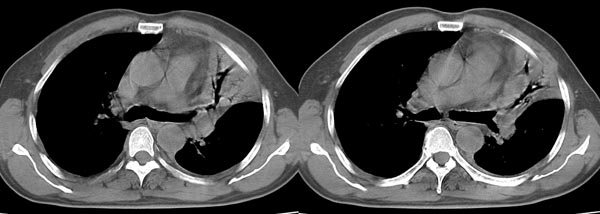

以下是引用dyqct在2006-4-1 22:20:00的发言:[br]左肺上叶明显萎陷、实变,支气管大部通畅,部分扩张,部分壁似见串珠状钙化。主动脉弓旁见肿大淋巴结。纵隔左移。左侧胸壁后缘见新月形高密度,边界清楚。[br] 考虑:1、左肺上叶肺不张伴支气管扩张(牵拉性),可能为支气管内膜结核所致。[br] 2、左侧少量胸腔积液。[br]

以下是引用piao001在2006-4-2 14:13:00的发言:[br]左肺上叶不全性不张,其内见钙化及扩张支气管,结合病史,考虑支气管内膜结核。建议支气管镜明确检查。